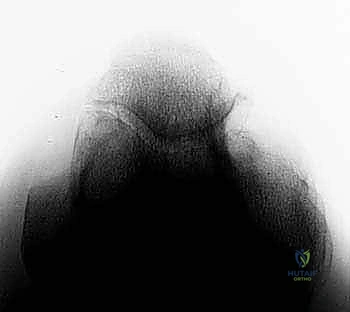

* الأشعة السينية (X-rays): ضرورية جداً لرؤية النتوءات العظمية (Osteophytes) في الناتئ المرفقي، وتضييق مساحة المفصل.

* الأشعة المقطعية (CT Scan): في بعض الحالات المعقدة، تُستخدم لبناء نموذج ثلاثي الأبعاد للمفصل للتخطيط الجراحي الدقيق قبل إدخال المنظار.

* التصوير بالرنين المغناطيسي (MRI): يُستخدم لتقييم الأنسجة الرخوة، وتحديداً حالة الرباط الجانبي الزندي (UCL)، والكشف عن وذمة نخاع العظم (Bone Marrow Edema) الناتجة عن الاصطدام المتكرر، وتقييم حالة الغضاريف.